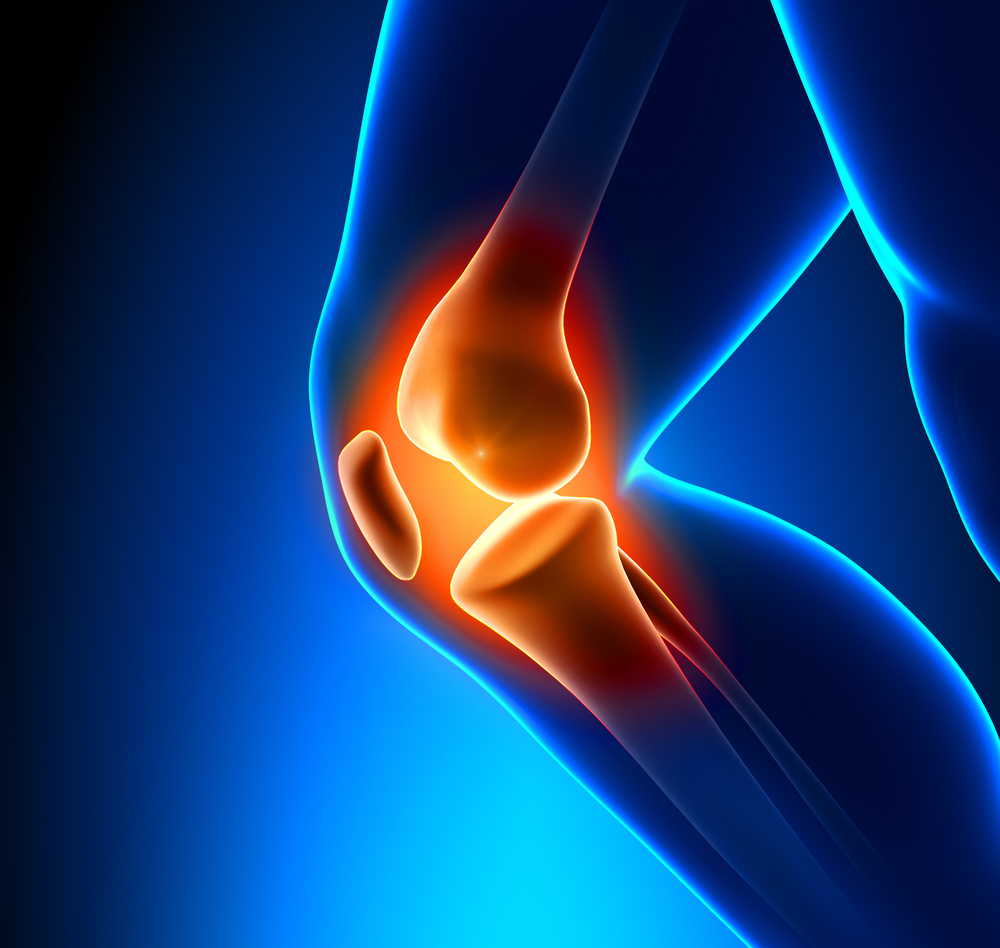

Joint Replacement

Because like all surgeries, joint replacement procedures do require some recovery time, they are normally only considered after all other non-surgical options have been discussed and/or attempted. Normally, joint surgery provides significant and wonderful results for the majority of patients. At Rothman Orthopaedic Institute, patients have the advantage of being seen by physicians who have actually helped develop and launch joint replacement techniques and who are considered to be well-renowned authorities on the topic of joint replacement

If you experience pain in any of your joints due to physical activities such as walking, running, and climbing stairs, it may be time to have a Rothman Orthopaedic Institute specialists diagnose your case. Joint replacement may be the answer for you. When simply sitting in a favorite chair or sleeping in your bed causes enough pain to wake you or make your life extremely uncomfortable, joint replacement may be able to get you back to an active lifestyle with less pain.